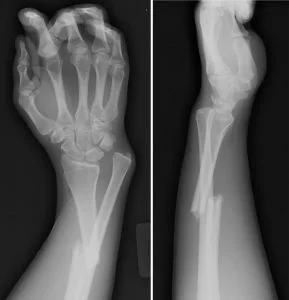

4.- Fractura de Galeazzi: Asocia una fractura distal del radio con una luxación de articulación radio-cubital distal. El mecanismo normalmente es por un traumatismo directo sobre la zona dorsal y externa, o un mecanismo indirecto por caída sobre la mano.